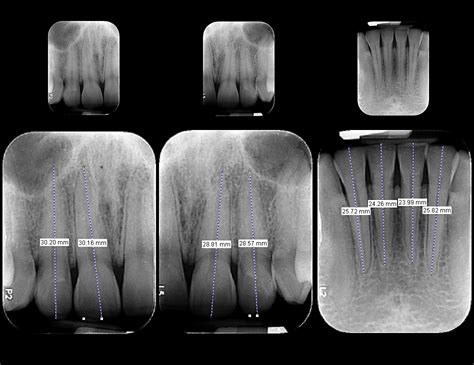

Las radiografías intraorales son aquellas en las que la película o el sensor se coloca dentro de la boca. Son las más comunes y detalladas, proporcionando una visión precisa de los dientes y las estructuras adyacentes.

- Radiografías periapicales: Muestran el diente completo, desde la corona hasta la raíz, y el hueso circundante.

Alta precisión y detalle: Proporcionan imágenes de alta resolución, lo que permite observar detalles minuciosos de los dientes, las raíces y las estructuras óseas circundantes.